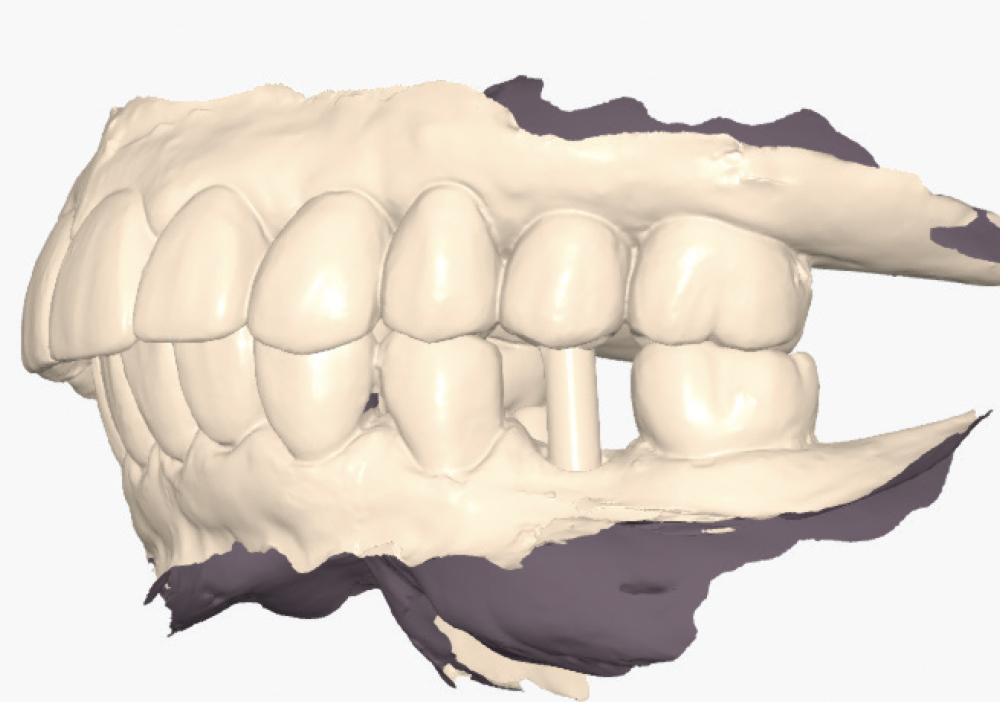

Implant post scan on left side of mouth

Implant post scan pointing down

Implant post scan close up